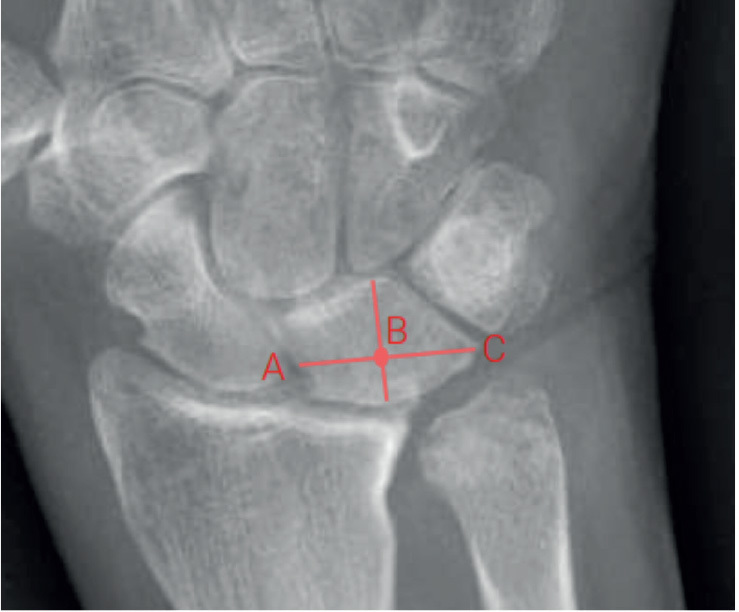

背景和目的:传统的尺桡关节远端关节炎(DRUJ)手术,通常涉及切除尺头,正日益受到新技术的挑战,如假体尺头置换术。本前瞻性队列研究的目的是调查经尺骨头置换术或切除术治疗的DRUJ关节炎患者术后2年的临床和患者报告的功能结果。方法:2015年至2020年间,40例因DRUJ病理而行尺骨头置换(n = 22)或尺骨头切除术(n = 18)的患者。术后3、6、12和24个月对患者进行随访,采用患者评定腕关节评估(PRWE)(主要结局)和手臂、肩部和手部残疾(DASH)问卷、疼痛、前臂旋转范围和握力(次要结局)。记录术后并发症。在24个月的随访中,分别有19名和16名患者有反应。女性和炎性关节炎在切除组中更为常见。一般线性回归分析调整诊断和基线PRWE评分我们的主要结局。结果:从基线到24个月,置换组PRWE的中位和四分位范围(IQR)改善为69 (IQR 49-87)至27 (IQR 6-48),切除组为60 (IQR 50-86)至23 (IQR 5-44),表明两组均较基线有所改善。在任何时间点未调整的估计没有差异。置换组和切除组24个月时PRWE调整平均值分别为35分和26分,平均差异为8.6分(95%可信区间-11.7 ~ 28.2),差异无统计学意义。我们发现,在任何时间点,任何次要结果的组间差异均无统计学意义。6例尺骨头置换术患者出现术后并发症,而尺骨头切除术患者无术后并发症报道。结论:短期内尺头置换术的疗效并不优于尺头切除术。

Background and purpose:  Traditional surgery for arthritis of the distal radioulnar joint (DRUJ), which typically involves resecting the ulnar head, is being increasingly challenged by newer techniques, such as prosthetic ulnar head replacement. The aim of our prospective cohort study was to investigate the clinical and patient-reported functional results, up to 2 years postoperatively, among patients with DRUJ arthritis treated with ulnar head replacement or resection.